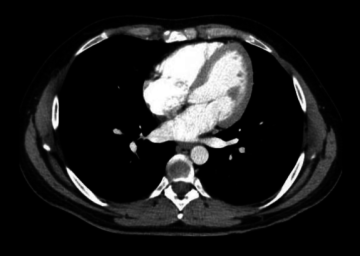

Scanner pulmonaire